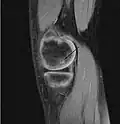

A large flap lesion in the femur head typical of late stage Osteochondritis dissecans. In this case, the lesion was caused by avascular necrosis of the bone just under the cartilage.